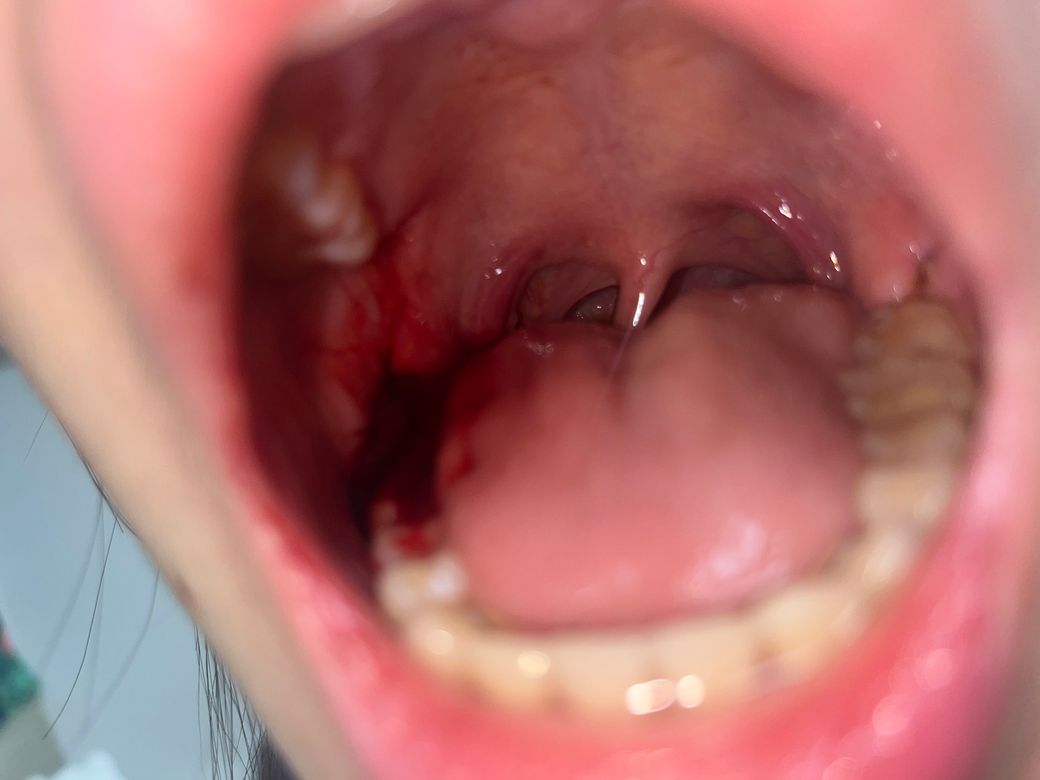

사랑니 발치 후 혈병이 너무 크고 피가 나서 계속 커져요

사랑니 발치 후 6시간 가량 지났습니다.

거즈는 2시간 반 정도 물었다가 뺐고, 냉찜질 하다 궁금해서 거울을 보니 혈병이 사랑니 바로 앞 어금니를 덮을 정도로 생겨 있고 송곳니와 윗니까지 피가 묻어 있습니다. 지혈이 덜 된 걸까요? 이대로 지내도 괜찮을까요?

• 1번 째 사진